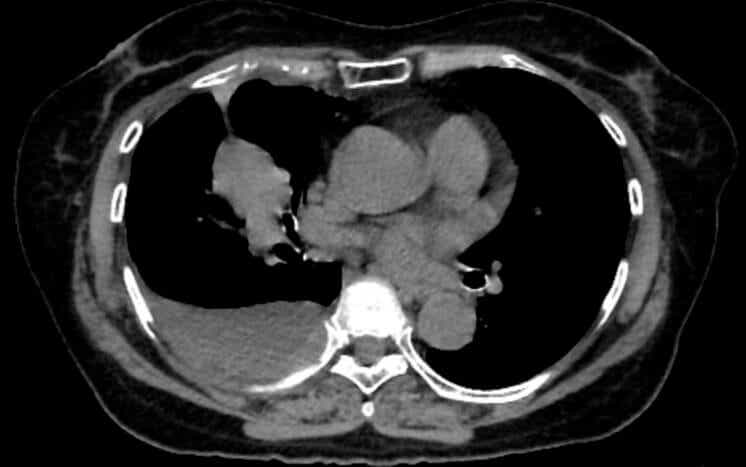

Coronary artery calcium, or CAC, is probably the best demonstration of what opportunistic screening can accomplish. When calcium builds up in the walls of the coronary arteries, it reflects underlying atherosclerosis, the disease process behind most heart attacks. CAC scoring is one of the strongest predictors of future heart attacks, and it adds predictive information beyond what traditional risk calculators provide.

Dedicated cardiac CT scans can measure this calcium precisely. So can a standard lung cancer screening CT, if someone takes the time to look. Studies have found that calcium measurements from lung screening CTs agree closely with those from dedicated cardiac scans, meaning the information is there even when the scan was not designed for cardiac evaluation.

That overlap matters because roughly 19 million noncardiac chest CTs are performed each year in the United States. Every one of those scans passes through the heart. The presence of calcium is visible in the images – yet studies find that when CAC is present, radiologists report it in fewer than half of cases.